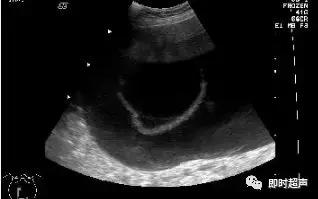

浆液性囊腺瘤(serous cystadenoma):为最常见的卵巢肿瘤,占卵巢肿瘤的27%。大部分为良性,但有较高的恶性变倾向,约有45%-50%可变为恶性。常为单侧性。图象特点:多为单房、壁薄、光滑、边界清,内部回声少,内有光带分隔为多房性,后壁回声增强。囊肿内壁显示有乳头状实质光团则为乳头状浆液性囊腺瘤。

浆液性囊腺瘤:单房或多房囊腺瘤边界清晰,囊壁薄而完整,内壁光滑,纤细分隔光滑均匀。乳突状囊腺瘤在囊内壁上突起乳头,其囊壁、囊内间隔及乳突上可见细条状血流。